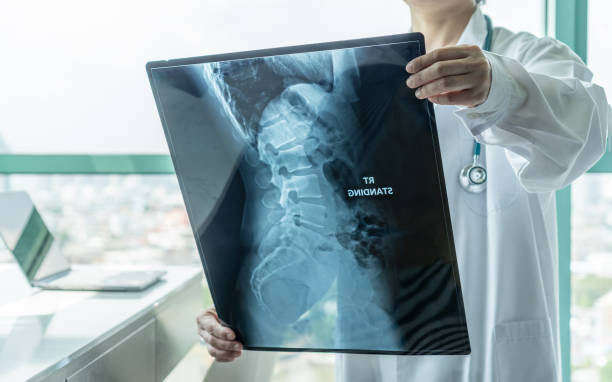

척추측만증의 수술은 어떤 방식으로 이루어지나요?

척추측만증의 수술은 주로 어린 아이들에게 권장되며, 척추 뼈가 아직 유연한 상태일 때 수행하는 것이 효과적입니다. 이 수술은 나사나 못을 사용하여 허리를 교정하는 것으로, 치과에서의 교정과 유사한 원리를 가지고 있습니다. 나사나 못을 이용하여 허리를 고정하고 철심을 사용하여 교정을 진행합니다. 이로써 허리를 바로 세우는 것이 가능하며, 수술 후에도 자연스러운 자세를 유지할 수 있습니다.